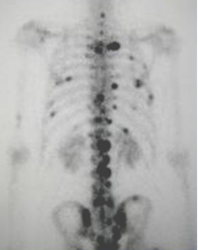

Fig 4 B. Gamagrafía ósea.

Enfermedad metastásica con múltiples focos de aumento en la actividad, de predominio en la columna, costillas y pelvis.